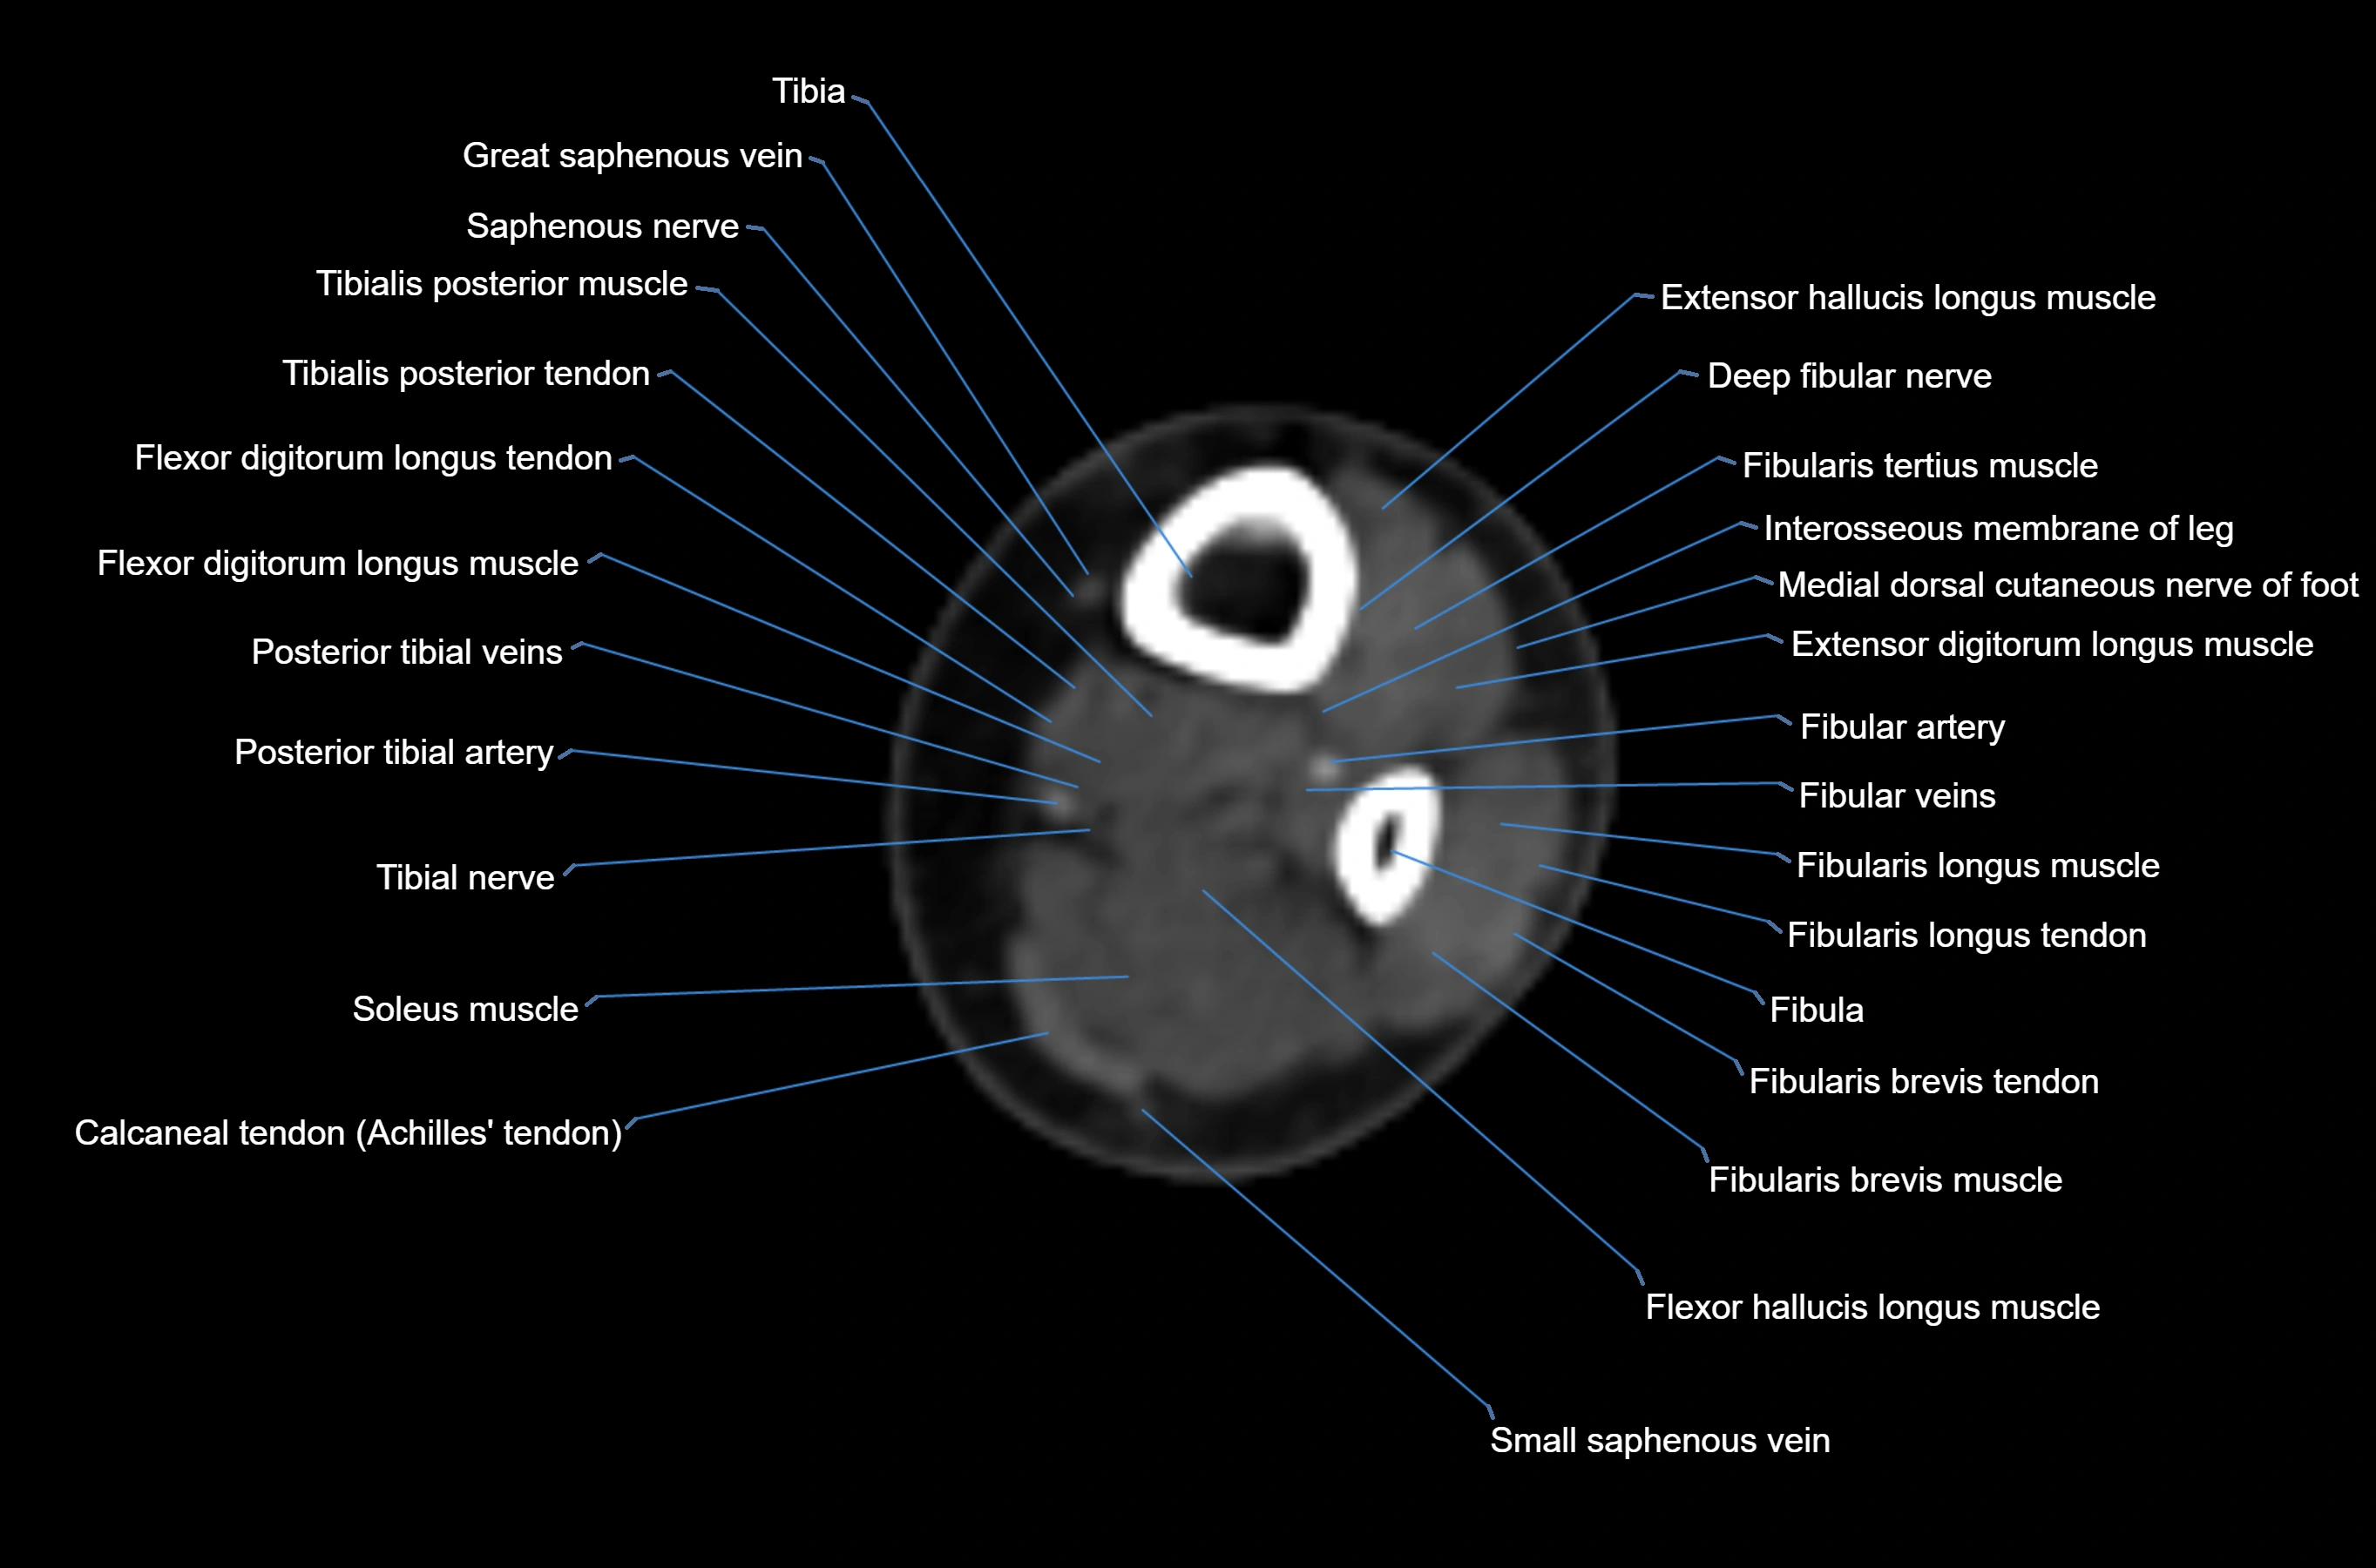

CT image